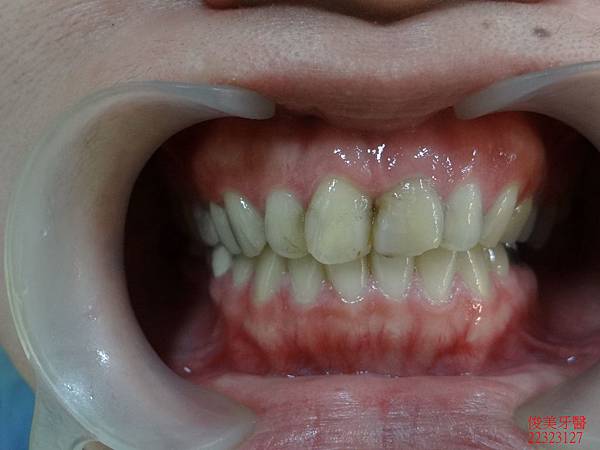

前面狀況。

牙齒排列不整。

牙縫蛀牙。